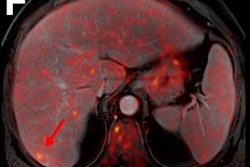

The company started a program that allowed participants to undergo PET/CT, noncontrast brain and pelvis MRI, and abdominal ultrasound exams every two years over a 10-year timespan. Employees could also undergo annual screenings such as chest x-ray, upper gastrointestinal x-ray with oral contrast, fecal occult blood test, prostate-specific antigen testing (for men over 55), and mammography (for women over 40). The program cost $1,350 per employee every two years; this cost was split between the company and participants.

For the imaging exams, employees were categorized into full participation (five screenings), partial (more than once and less than five), and no participation groups. Anzai's team measured the cancer detection rate, rate of cancer-related death, and cancer-related costs of care. Of 1,213 employees, 543 were full participants, 318 were partial, and 352 did not participate in the imaging protocol. Across all three groups, 54 cancers were identified, with the majority in the full and partial participation groups being early stage (0 to 1).

The study showed that whole-body cancer screening did reduce cancer-related mortality and costs of cancer care, but it did not statistically significantly increase the cancer detection rate.